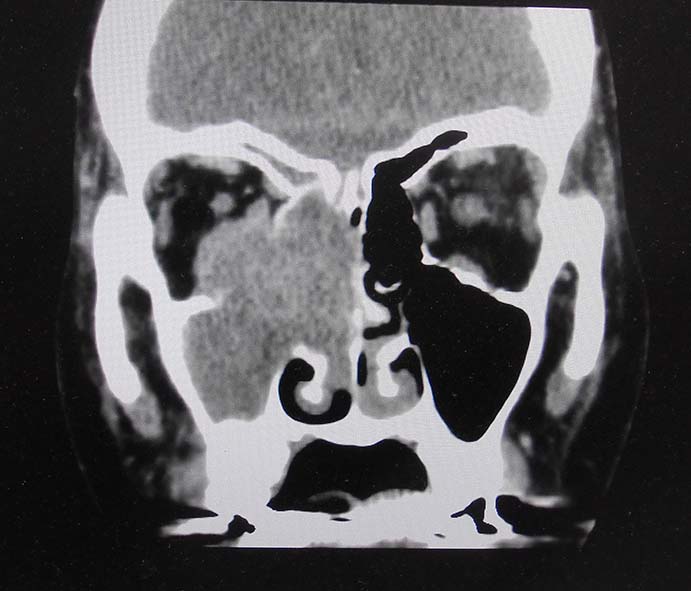

CT所見

副鼻腔腫瘤生検組織

日本病理学会中部支部交見会のスライドより。(S.Suzuki Dr.)

NUT03.jpg NUT04.jpg

詳細は以下のcase reportをご参照ください。

Suzuki S, Kurabe N, Minato H, Ohkubo A, Ohnishi I, Tanioka F, Sugimura H.

A rare Japanese case with a NUT midline carcinoma in the nasal cavity: a case report with immunohistochemical and genetic analyses. Pathol Res Pract. 2014 Jun;210(6):383-8. doi: 10.1016/j.prp.2014.01.013. Epub 2014 Feb 22. PMID:24655834